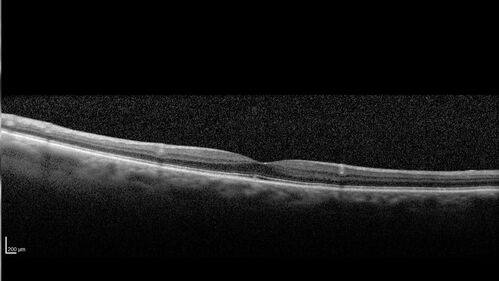

Large Hyper-reflective drusen in age-related macular degeneration

69 year old healthy woman with 20/20 vision and no visual complaints